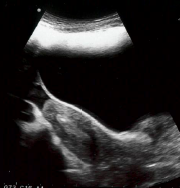

Het proces is te volgen doordat er gebruik wordt gemaakt van echoscopie via de buik.

De binnencatheter wordt in de buitencather geschoven en zo in de baarmoederholte gebracht door de arts. Het embryo wordt met een zeer kleine hoeveelheid vloeistof en lucht in de baarmoederholte gespoten. Deze kleine hoeveelheid lucht is te zien voor u als luchtbellen op het echobeeld. Dit is de plek waartussen het embryo is teruggeplaatst.

Baarmoeder

Witte luchtbel is zichtbaar in de baarmoeder na plaatsing van het embryo